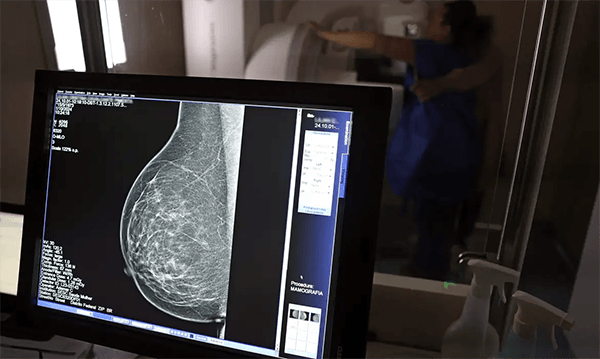

O Ministério da Saúde passou a recomendar o acesso a mamografia, via Sistema Único de Saúde (SUS), para mulheres de 40 a 49 anos – mesmo que não haja sinais ou sintomas de câncer de mama. De acordo com a pasta, a faixa etária concentra 23% dos casos da doença, e a detecção precoce aumenta as chances de cura. Até então, a orientação era que o exame fosse feito a partir dos 50 anos.

A medida faz parte de um conjunto de ações anunciadas nesta semana voltado para a melhoria do diagnóstico e da assistência. A recomendação para mulheres a partir dos 40 anos é que o exame seja feito sob demanda, em decisão conjunta com o profissional de saúde.

As mamografias via SUS em pacientes com menos de 50 anos, de acordo com a pasta, representam 30% do total, o equivalente a mais de 1 milhão apenas no ano de 2024.

Outra medida anunciada é a ampliação da faixa etária para o rastreamento ativo – quando a mamografia é solicitada de forma preventiva a cada dois anos. A idade limite, até então, era 69 anos. Agora, passa a ser 74 anos. Dados do ministério revelam que quase 60% dos casos de câncer de mama estão concentrados entre 50 e 74 anos.

Os números mostram que, em 2024, cerca de 4 milhões de mamografias para rastreamento e 376,7 mil exames diagnósticos foram realizados no SUS.